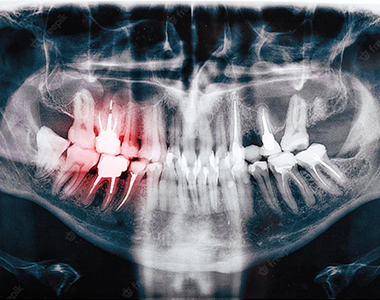

What will an X-ray show?

X-rays can show decay that may not be seen directly in the mouth: for example, under a filling, or between the teeth. They can show whether you have an infection in the root of your tooth and how severe the infection is.

In children, an x-ray can show any teeth that haven’t come through yet, and show the dental team whether there is enough space for the teeth to come through. In adults, it can show any impacted wisdom teeth that may need to be removed, before they cause any problems.